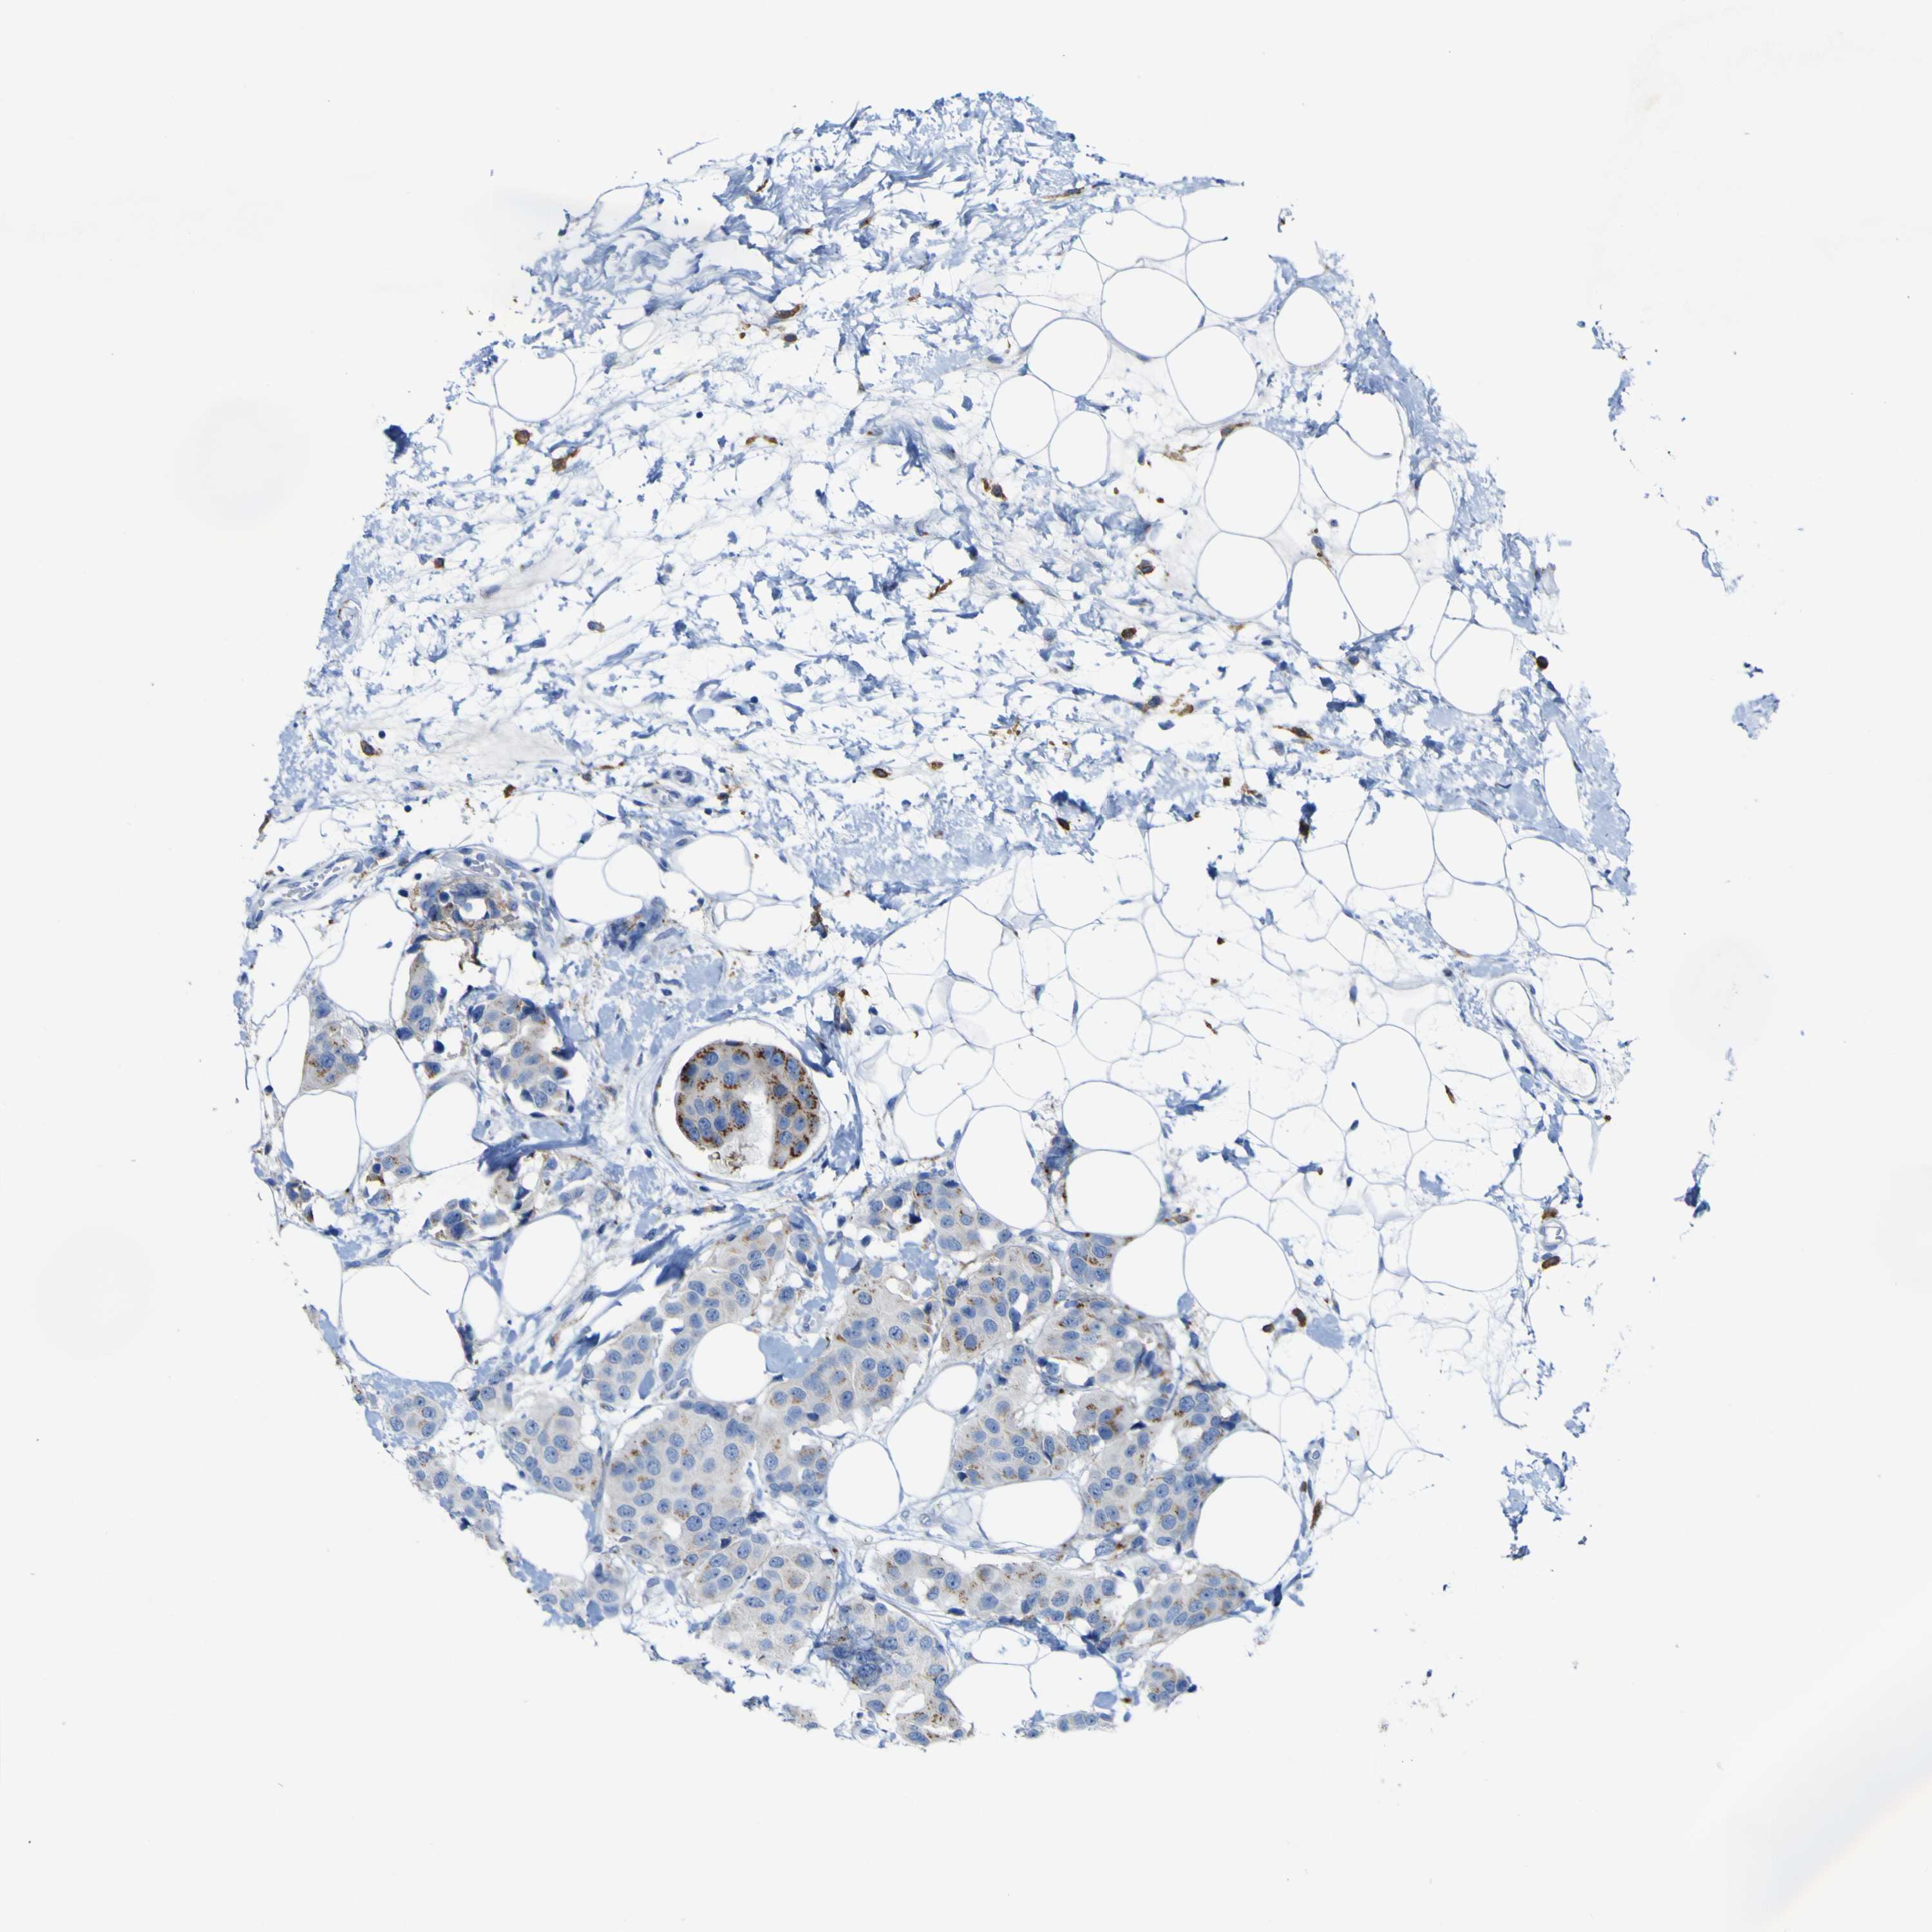

CANCER BREAST CANCER Show tissue menu

BRCA TCGA BRCA VALIDATION PROTEIN EXPRESSION

ANTIBODIES

AND

VALIDATION